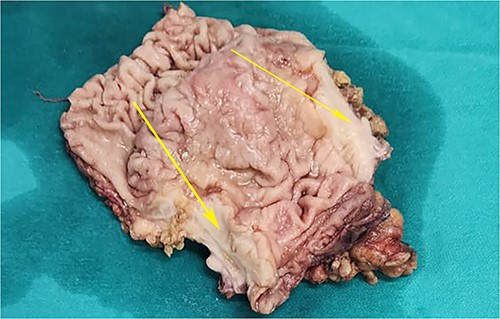

On laparotomy, the gastric antrum was infiltrated with a tumour with no serosal extension (Fig. 4), no ascites, and bilateral ovarian cysts (right: 12 × 10 × 6 cm, left: 9 × 5 × 4 cm) (Fig. 5). An R0 resection that included D2 gastrectomy and pan-hysterectomy was performed. The patient made an uneventful recovery and was discharged on the 15th postoperative day. The final diagnosis after histopathological examination was diffuse infiltrating gastric carcinoma signet cell-type (Figs 6 and 7), LP, KT deposits in both the ovaries (Fig. 8), with regional lymph node involvement (Fig. 9) in two nodes among the 15 nodes that were dissected. The staging was T4a, N1, and M1. The patient decided against adjuvant treatment. She was disease-free on clinical and radiological examinations at 12 months.

Postoperative specimen of the right ovarian cyst showing solid areas within (arrows).